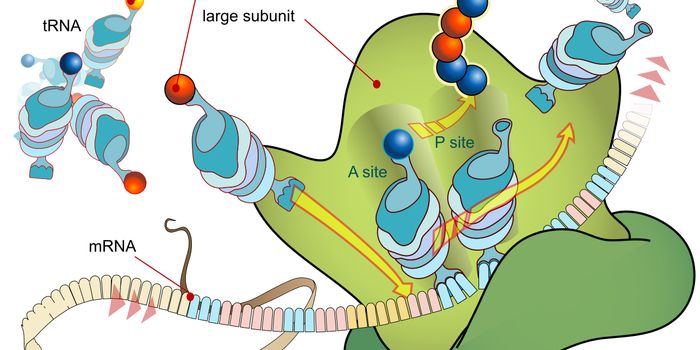

SEP 11, 2024Clinical & Molecular DXRNA does many things in the body. Now, scientists have shown that RNA in blood samples can be used as a diagnostic indic ...

AUG 26, 2024Genetics & GenomicsCells are defined by the genes they express. In human cells, there are thousands of different protein coding genes, and ...

AUG 13, 2024Genetics & GenomicsResearchers have recently discovered a novel type of RNA known as circular RNAs (circRNAs). These molecules form when co ...

AUG 12, 2024Genetics & GenomicsWhile human genes tend to have a start and stop site, not all gene transcripts are the same. Researchers have identified ...

JUL 30, 2024Genetics & GenomicsFor a long time, gene expression seemed fairly straightforward. But in recent years, researchers have revealed many surp ...

JUL 26, 2024Cell & Molecular BiologyResearchers are learning more about genomic sequences that are transcribed but never translated into protein, and once w ...